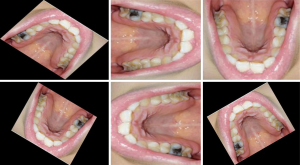

Training deep neural networks requires a large amount of reasonable data, and too small a data set can lead to overfitting of the neural network. In this study, we used data augmentation techniques to increase the amount of data in the acquired dataset, thereby improving the generalization ability and robustness of the model. The original and augmented images are shown in Figures 4,5, respectively, and the annotation files corresponding to each image were transformed simultaneously during this process. The images of 570 participants were expanded to 3,990 for training purposes, and the images of 70 participants were divided into a separate test set.

Firstly, all collected oral images were labelled for dental caries using LabelImg software; secondly, 570 of the images were expanded to 3,990 using the data augmentation technique and the data set was divided into a training set and a test set according to a certain ratio. The training set contained 3,990 images from 570 volunteers, while the test set contained 70 images from 70 volunteers. We ensured that the 2 subsets, the divided dataset and the test set, were mutually exclusive. Finally, the experiment was divided into 3 parts: the first part used the 3,990 images from the 570 images as the original group, the model was trained using the YOLOv3 algorithm, and test the model was trained using the independent test set; the second part used the image enhancement technique to enhance the images as the original group while keeping the number of images in the original group unchanged. In the third part, the original group data and the enhancement group data were mixed to form the comprehensive group, and the comprehensive group data set consisted of 7,980 images.